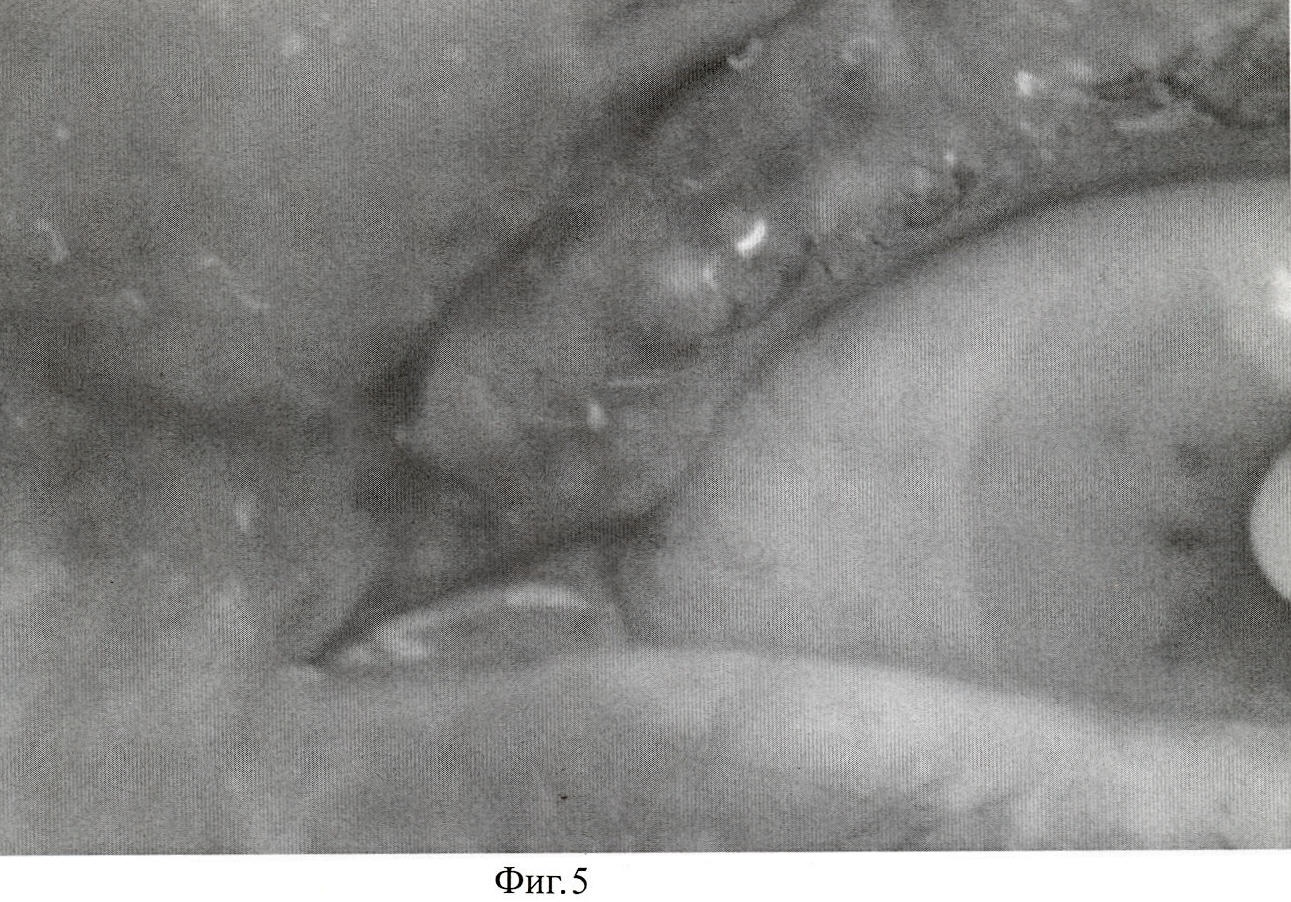

Пациентка Н. 75 лет.

Диагноз: Новообразование кожи левого верхнего века. (Фиг.4).

Пациенту перорально дают препарат «Аласенс» в дозе 15 мг/кг веса, растворяя его в обычной воде. Через 3 часа после введения препарата пациента усаживают перед экраном из высокопоглащающей ткани. С помощью 2 люминесцентных ламп с максимумами излучения 390, 415 и 433 нм, укрепленных на кронштейнах, добиваются максимально равномерного освещения возбуждающим излучением зоны новообразования. Производят регистрацию интересующего участка цифровой камерой с RGB CCD-матрицей. На полученном трехканальном изображении (Фиг.5) с помощью программы для ЭВМ CancerPlot оценивают долю участия красного канала, соответствующего флуоресценции протопорфирина-IX (Фиг.6). Доля участия красного канала в флуоресцентном изображении интрадермального невуса (Rtum) составила 33.87%. Доля участия красного канала в флуоресцентном изображении окружающей кожи (Rcut) составила 27.89%.

Rdiff=((33.87-27.89)/27.89)·100%=21.4%

Колориметрический отход по R-каналу на флуоресцентном изображении новообразования составил +21.4%, что больше +10%. Полученный результат говорит в пользу злокачественного характера опухоли. Гистологический диагноз (базально-клеточный рак кожи) подтвердил злокачественный характер новообразования.